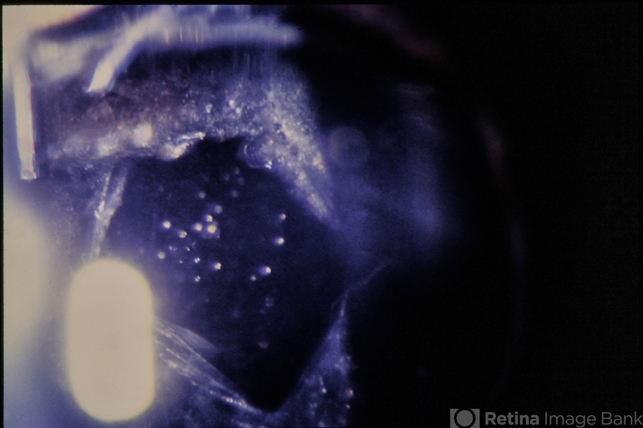

- posterior capsule opacification, color photo, laser

- Color photo of PCO, s/p YAG capulotomy.